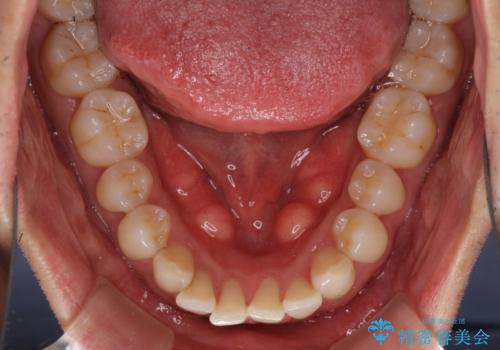

- 口の閉じにくさを気にして来院された患者様です。

患者様と相談の上、横顔の印象から抜歯矯正は必要ないと判断し、IPR(歯と歯の間)並びに歯列全体の後方移動により口元の突出感の改善することとしました。

しっかりと装着時間を守り、ゴムかけも徹底していただいたので、思いの外口元を引っ込めることができました。

これ以上の改善を望まれましたが、非抜歯矯正でこれ以上口元を引っ込めると食いしばりすやすい咬合となるため、この歯列で終了としました。